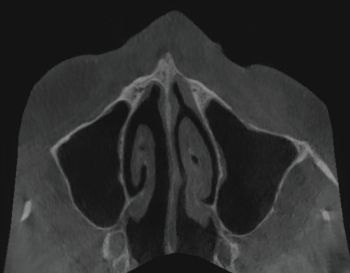

X-rays exams (i.e. OPG and CBCT) revealed the position of the displaced implant, which subsequently migrated near the ostiomeatal complex (OMC). It’s worth pointing out that immediately after their displacement, dental implants are usually located on the floor of the maxillary sinus or in the immediate vicinity; after a while, the displaced implants start to migrate against the gravitational force in the direction of the maxillary sinus ostium (as reported in the present clinical case) thanks to the strong mucociliary clearance by the sinus mucosa as well as nasal and intrasinus pressure changes. Notably, no reactive changes of the sinus membrane were observed (Figs. 1–5).

Fig. 4: Pre-op CBCT radiographic exam (axial section)